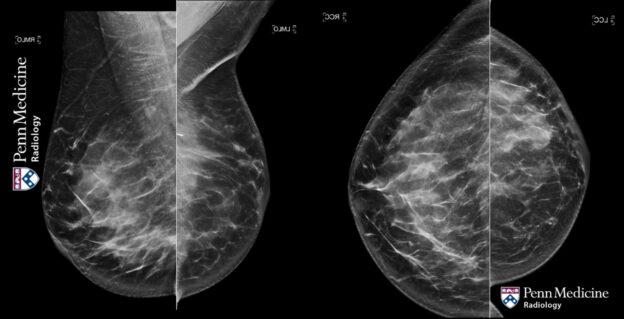

40-year-old woman with breast asymmetry

A 40-year-old woman with no significant past medical history and a family history of breast cancer in two first-degree relatives presented for screening mammography.